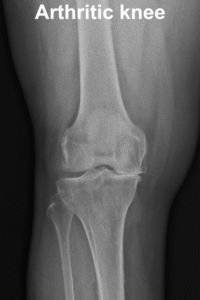

Osteoarthritis is a degenerative joint condition where the cartilage covering the ends of bones in the knee joint gradually wears away, leading to pain, stiffness, and reduced movement in the knee. In a healthy knee joint, cartilage provides a smooth, cushion-like surface that lets the bones move against each other with minimal friction and absorbs shock during weight-bearing activities. With osteoarthritis, this cartilage becomes thinner and rougher, so the bones begin to rub more closely against each other resulting in pain, swelling and stiffness.